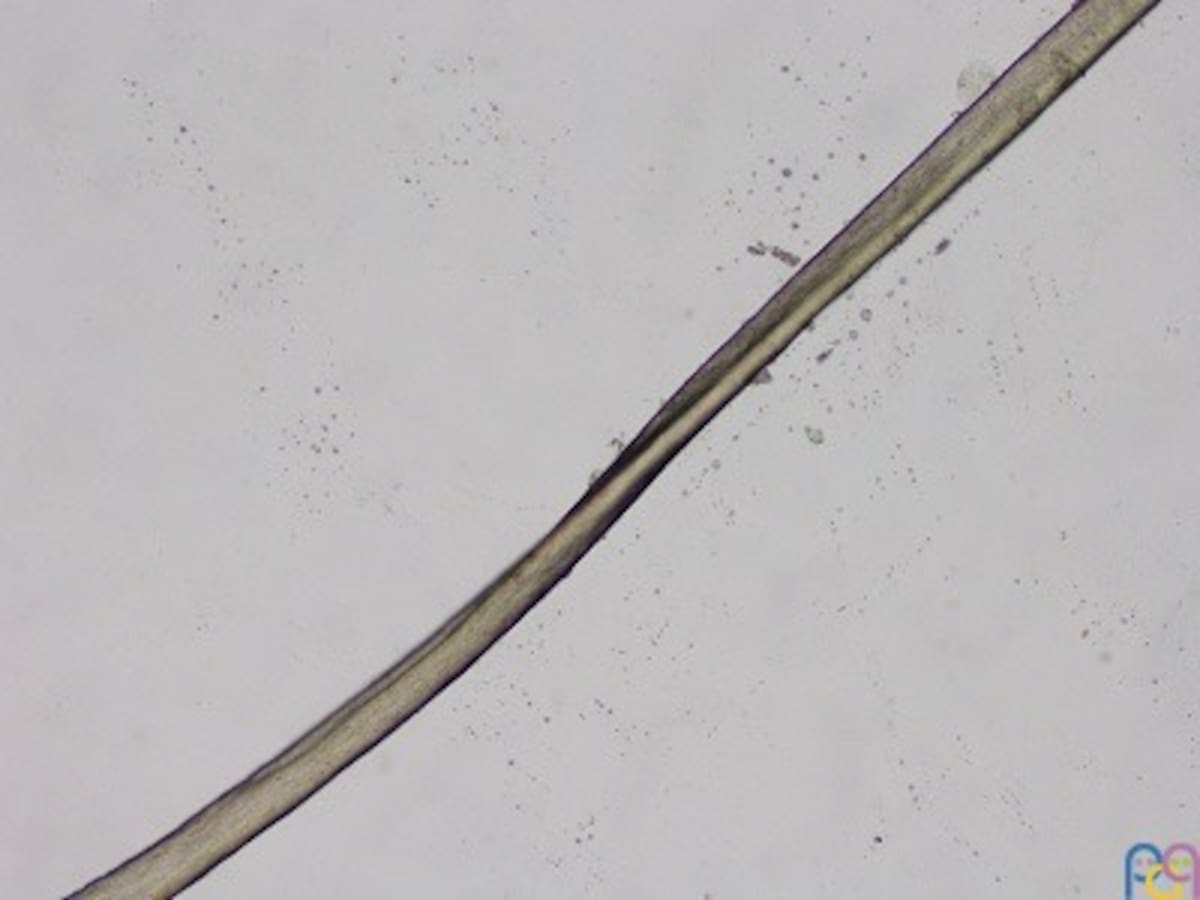

Cuando se observa el cabello bajo un microscopio electrónico, los especialistas pueden distinguir fácilmente la forma triangular o irregular del tallo capilar, lo que confirma el diagnóstico.